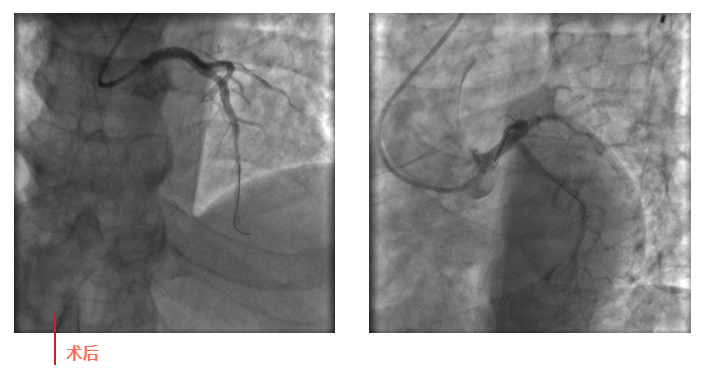

心血管內(nèi)科副主任徐先進(jìn)在主任助理農(nóng)彥林和主任汪念東的配合下行冠狀動(dòng)脈造影,結(jié)果如術(shù)前判斷一致,左主干重度狹窄,患者命懸一線。對(duì)團(tuán)隊(duì)緊急處置非常信任的李阿姨,毫無疑慮地聽取了術(shù)者的建議,同意在血管內(nèi)超聲(IVUS)的精準(zhǔn)指導(dǎo)下,在患者左主干內(nèi)植入一枚支架,成功拯救了患者的生命。

術(shù)后,患者轉(zhuǎn)入心血管內(nèi)科CCU病房,在IABP泵的支持下渡過了危險(xiǎn)期。李阿姨紅著眼眶坐在床邊,仍心有余悸,“還好有你們啊!真是太謝謝了!”經(jīng)過心血管內(nèi)科團(tuán)隊(duì)的精心治療和護(hù)理,患者現(xiàn)已康復(fù)出院。